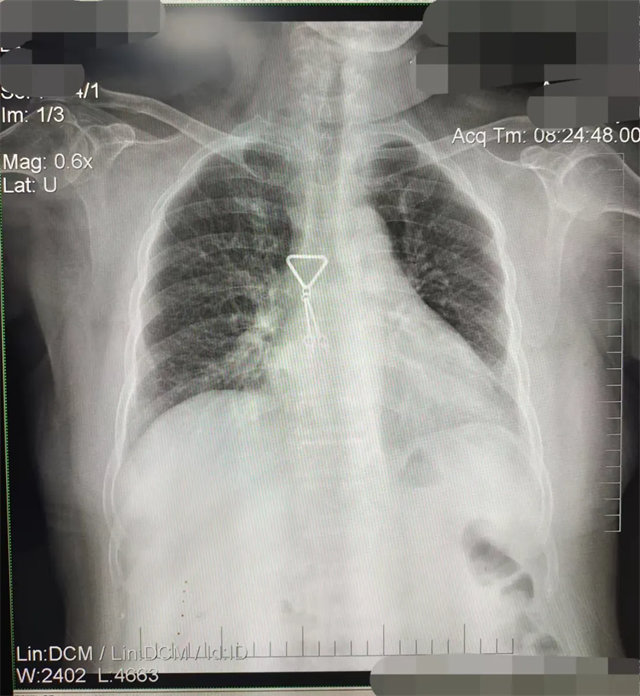

缺陷:肩胛骨未完全拉離肺野,吸氣不完全,存在金屬偽影遮擋,略有聳肩,且肺尖顯示不好,圖像顆粒感較強,管電流量不夠,信噪比偏低。

解決:去除金屬物品后,按標準體位,使患者雙肩旋前與前胸一并緊貼成像件,適當(dāng)調(diào)高mAs,然后深吸氣后屏氣曝光。